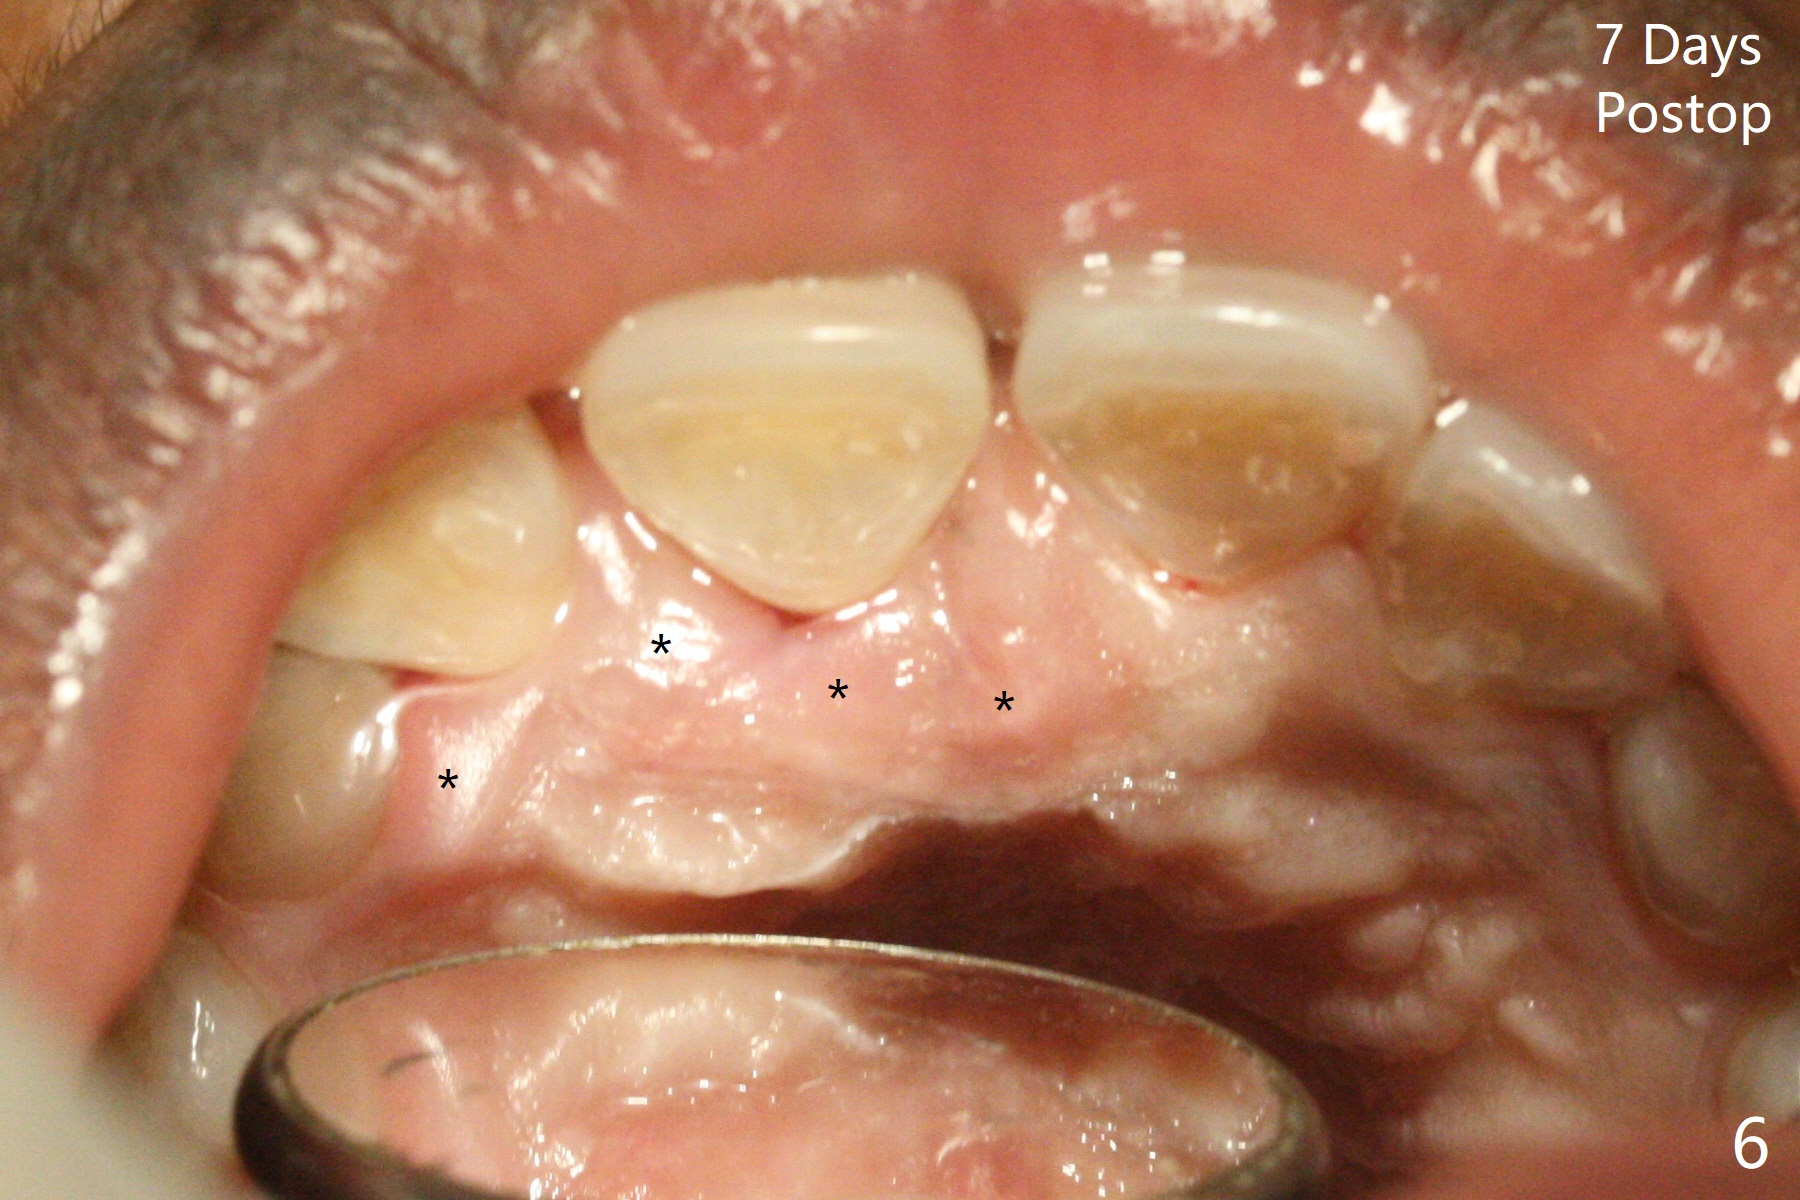

50岁女8号牙远中颊侧冠方移位(图一),牙根暴露(*),前磨牙-前磨牙开合,腭侧牙龈红肿。拔除清创后,使用导板钻洞,徒手植入2.5x13毫米一段式植体,首先将PRF膜插入腭侧,剩余牙槽窝空间植入粘性骨粉(图二:*)。截断拔除牙齿,牙冠掏空,反复调整牙冠长度,使用流动性树脂(flowable composite,图三:*)衬里固定牙冠(C),恰好PRF封闭远中颊侧牙槽窝开口(图四),自然牙冠和一段式植体配合,形成最佳emergency profile,最后牙周敷料进一步封闭牙槽窝(图五),防止骨粉早期脱落,不必担忧敷料不透气。腭侧牙龈红肿(图六)。服用Augmentin两天,患处没有触痛了(图七)。术后九天颊侧牙龈继续延长(图八).